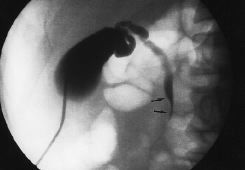

Radiología Biopsia percutánea de lesiones del tubo digestivo guiada por ecografía

Biopsia percutánea de lesiones del tubo digestivo guiada por ecografía

Ultrasound-guided percutaneous biopsy of digestive tract lesions